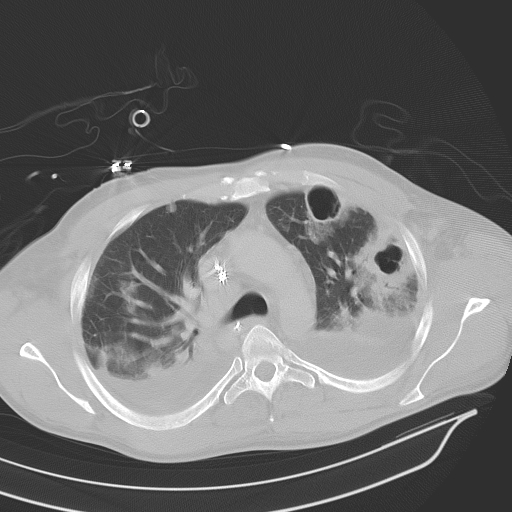

폐농양을 진단하는 데는 보통 가슴 X선이나 컴퓨터 단층촬영(CT)과 같은 영상 검사들이 사용됩니다. 이러한 검사들은 폐 안에 공동이 존재하는지 여부를 확인하는 데 도움을 줍니다. 혈액 검사 및 가래 배양 검사를 통해 원인균을 확인하고 적절한 항생제 치료를 결정할 수도 있습니다. 일부 경우에는 기관지경 검사가 필요할 수 있으며, 이를 통해 농양으로부터 직접 샘플을 채취하거나 질환의 원인이 되는 폐색을 제거할 수 있습니다. 폐농양 치료는 보통 장기간의 항생제 치료로 시작하며, 종종 정맥 주사를 통해 투여됩니다. 항생제의 선택은 배양 검사 및 민감도 검사 결과에 따라 결정되며, 특정한 원인균을 목표로 하는 치료가 이루어집니다. 항생제에 반응하지 않거나 농양이 특히 큰 경우, 수술적 개입이 필요할 수 있습니다. 이 경우 농양을 바늘이나 튜브를 통해 배액 하거나, 심한 경우에는 폐의 일부를 제거하는 수술이 필요할 수 있습니다. 보조 치료로는 산소 요법과 호흡 재활 치료가 필요할 수도 있으며, 환자가 완전히 회복할 수 있도록 돕습니다. 환자의 상태가 호전되는지, 악화되는지에 대한 면밀한 관찰이 필요하며, 농양이 제대로 치료되지 않으면 패혈증이나 흉막삼출증과 같은 합병증이 발생할 수 있습니다. 조기 및 적극적인 치료는 이러한 심각한 결과를 예방하고 완전한 회복을 보장하는 데 필수적입니다.